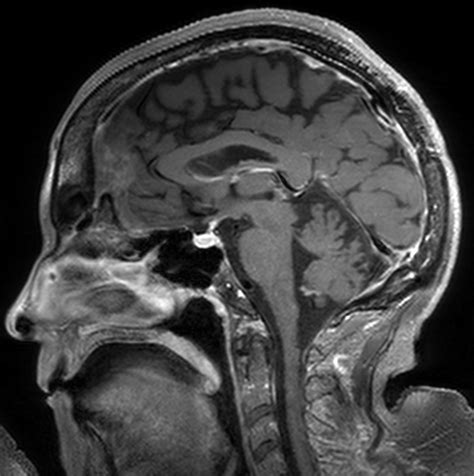

The human brain is a dynamic organ that undergoes various changes throughout a lifespan. Parenchymal volume loss, or cerebral atrophy, is essentially the loss of neurons and the connections between them. As the brain loses these cells, the physical space they occupied diminishes. This can manifest as an expansion of the sulci (the grooves on the surface of the brain) or the enlargement of the ventricles (the fluid-filled spaces inside the brain).

Brain MRI imaging scan

Technological advancements in "volumetric MRI analysis" now allow doctors to quantify brain volume more precisely than in the past. These automated programs can compare a patient's brain size to normative databases, providing a more objective measure of whether the observed loss is truly abnormal for the patient's specific age and biological sex.